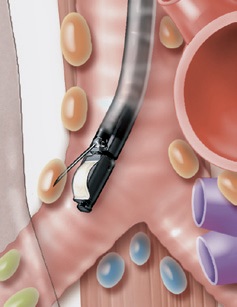

Многофункциональная конструкция

Модель EB-1970UK оснащена рабочим каналом диаметром 2,0 мм трансбронхиальной аспирационной биопсии под контролем эндоскопического ультразвукового исследования (TBNA). Эта процедура позволяет поставить точный диагноз и уточнить стадию процесса.